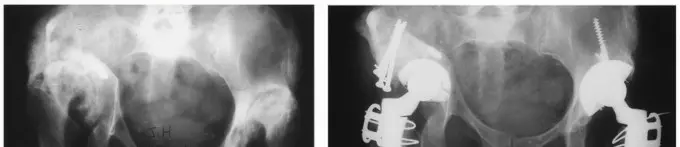

الخلاصة الطبية الموسعة: استبدال مفصل الورك بالسيقان المعيارية يمثل طفرة نوعية في جراحة العظام، مقدمًا حلاً متقدمًا ومخصصًا للمرضى الذين يعانون من تلف شديد في مفصل الورك، وخاصة أولئك الذين يعانون من تشوهات معقدة أو خضعوا لعمليات جراحية سابقة. هذه التقنية تتيح للجراحين مرونة غير مسبوقة في إعادة بناء ميكانيكا الورك الطبيعية بدقة متناهية، مما يضمن أفضل النتائج من حيث تخفيف الألم واستعادة الوظيفة الكاملة للمفصل. في صنعاء، يقف الأستاذ الدكتور محمد هطيف في طليعة هذا المجال، بصفته أستاذًا في جامعة صنعاء وخبرة تتجاوز العقدين، ويُعرف بدمجه لأحدث التقنيات مثل الجراحة المجهرية (Microsurgery)، تنظير المفاصل 4K (Arthroscopy 4K)، وجراحة المفاصل (Arthroplasty) لتقديم رعاية استثنائية تتميز بالدقة والاحترافية والنزاهة الطبية الصارمة.